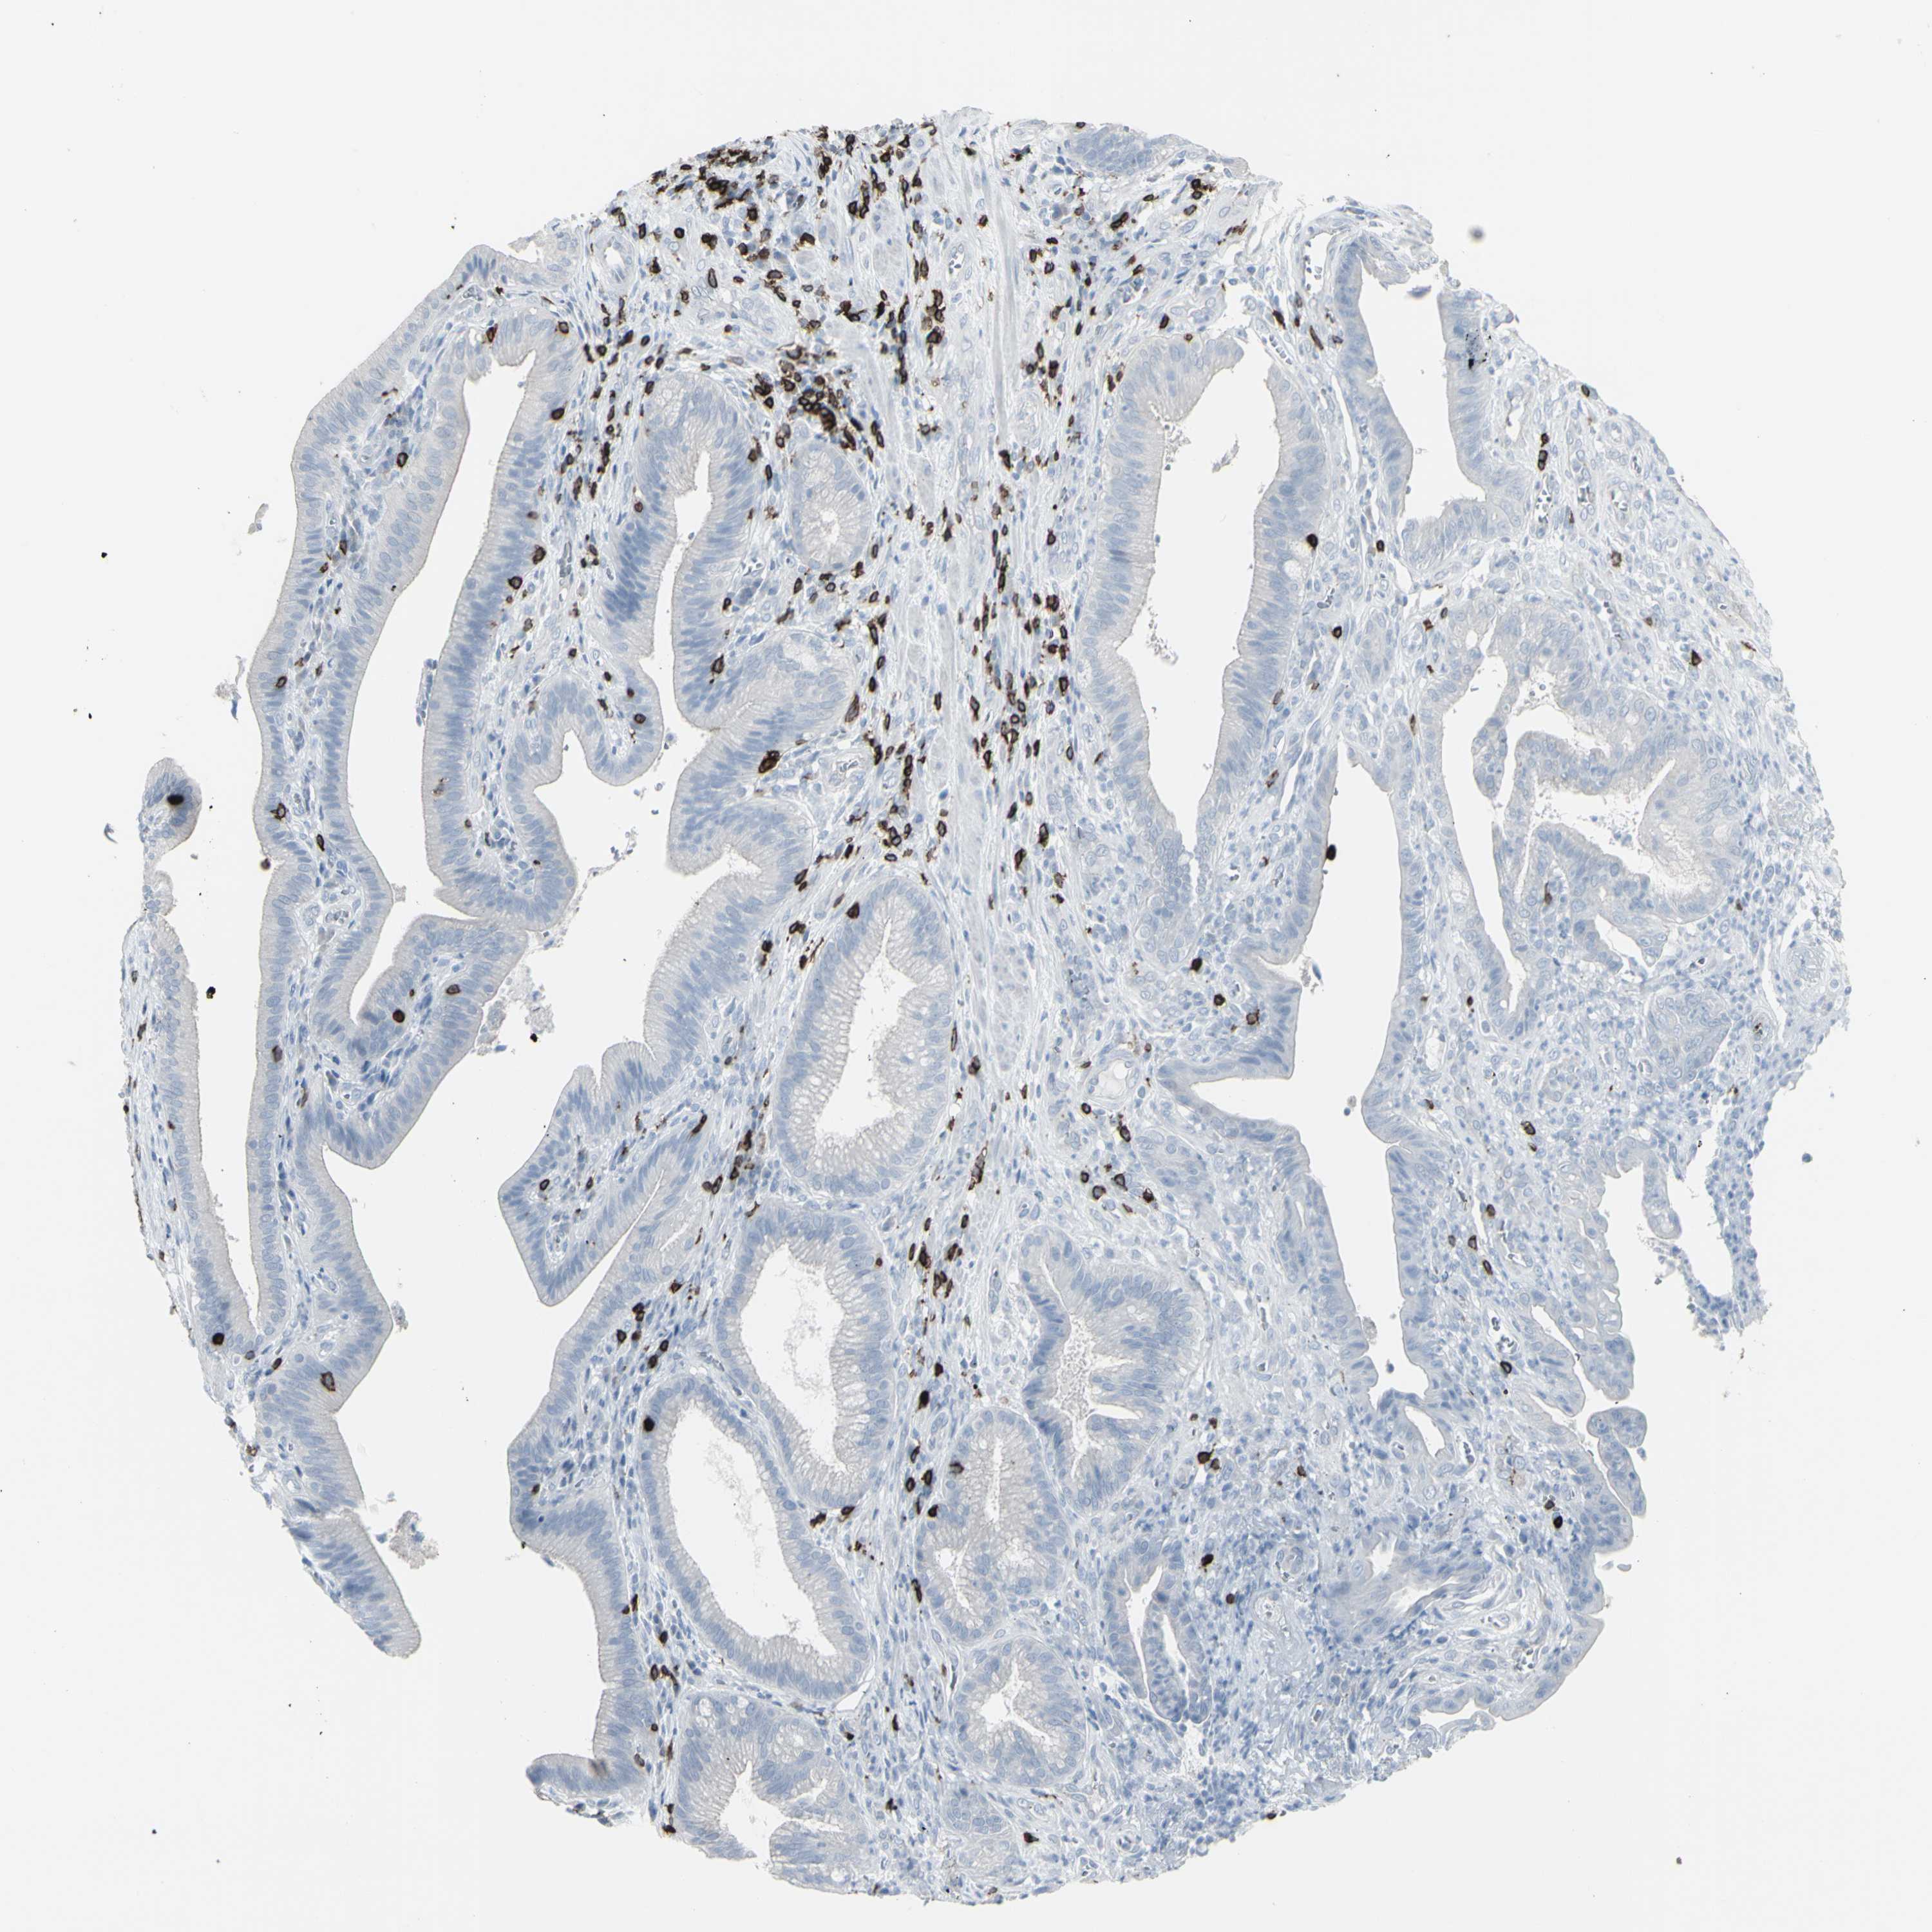

PANCREATIC CANCER - Protein expressioni

A mouse-over function shows sample information and annotation data. Click on an image to view it in a full screen mode. Samples can be filtered based on level of antibody staining by selecting one or several of the following categories: high, medium, low and not detected. The assay and annotation is described here.

Note that samples used for immunohistochemistry by the Human Protein Atlas do not correspond to samples in the TCGA dataset.

Antibody stainingi

Antibody staining in the annotated cell types in the current human tissue is reported as not detected, low, medium, or high, based on conventional immunohistochemistry profiling in selected tissues. This score is based on the combination of the staining intensity and fraction of stained cells.

Each image is clickable and will lead to virtual microscopy that enables deeper exploration of all samples and also displays staining intensity scores, fraction scores and subcellular localization as well as patient and tissue information for each sample.

Antibody HPA008750

Antibody CAB004651

Staining

High

Medium

Low

Not detected

Intensity

Strong

Moderate

Weak

Negative

Quantity

>75%

75%-25%

<25%

None

Location

Nuclear

Cytoplasmic/membranous

Cytoplasmic/membranous,nuclear

Adenocarcinoma, NOS

Adenocarcinoma, metastatic, NOS